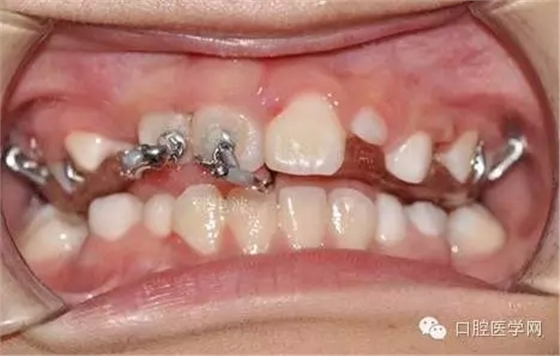

鏈狀正畸牽引裝置粘固后的口內(nèi)情況

帶入口內(nèi)調(diào)整吊桿方向加輕力:

(咬合調(diào)整好,加輕力激活)

每周復(fù)診:清洗,加力,適當(dāng)調(diào)整吊桿方向

用時(shí)9周完成埋伏牙牽引。